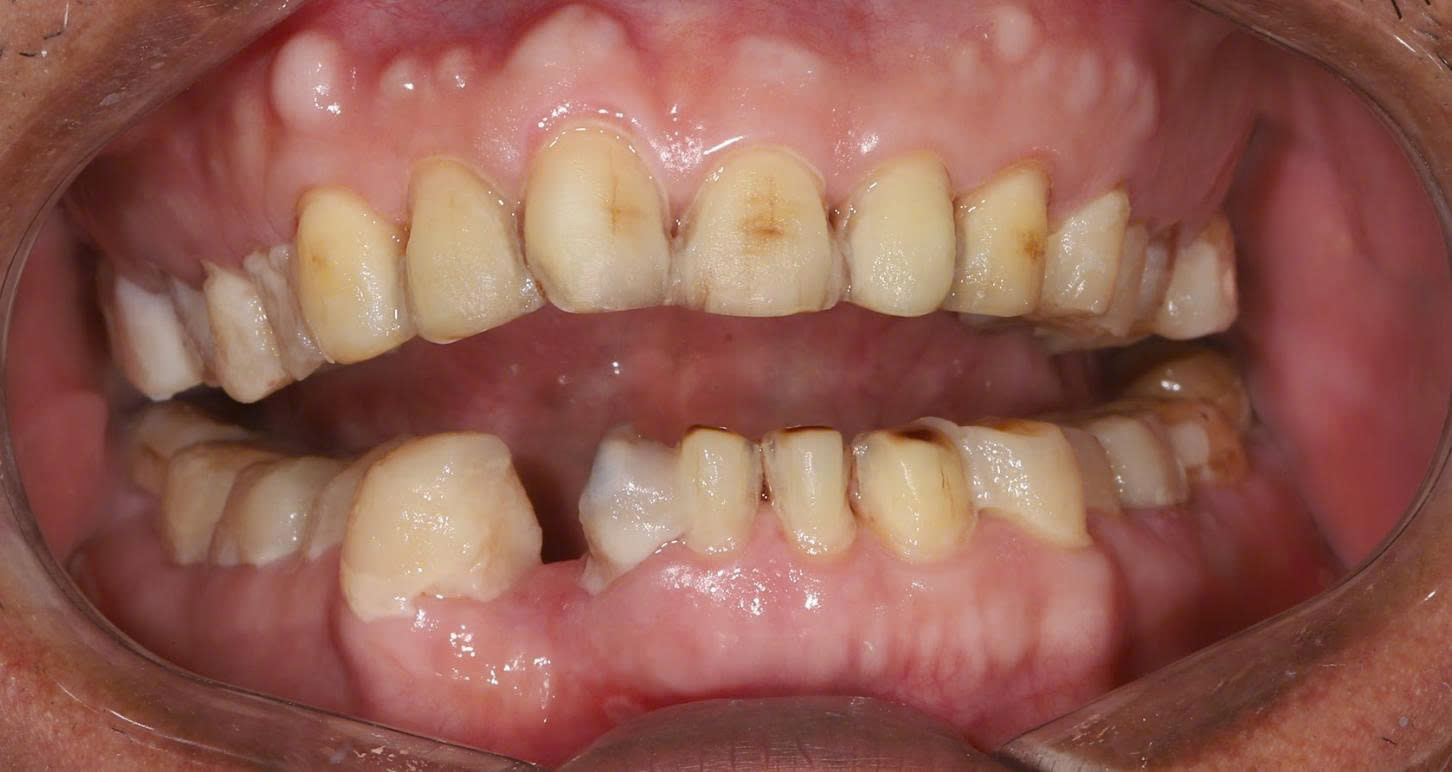

3.1 Khám trong miệng

-

Hầu hết các răng hai hàm đã bị mài nhỏ quá mức

Răng số 8 (răng khôn) bị mài và bọc sứ – hoàn toàn sai chỉ định

Viền lợi không đều, có dấu hiệu viêm quanh răng

Bệnh nhân phản ánh đau nhức âm ỉ kéo dài